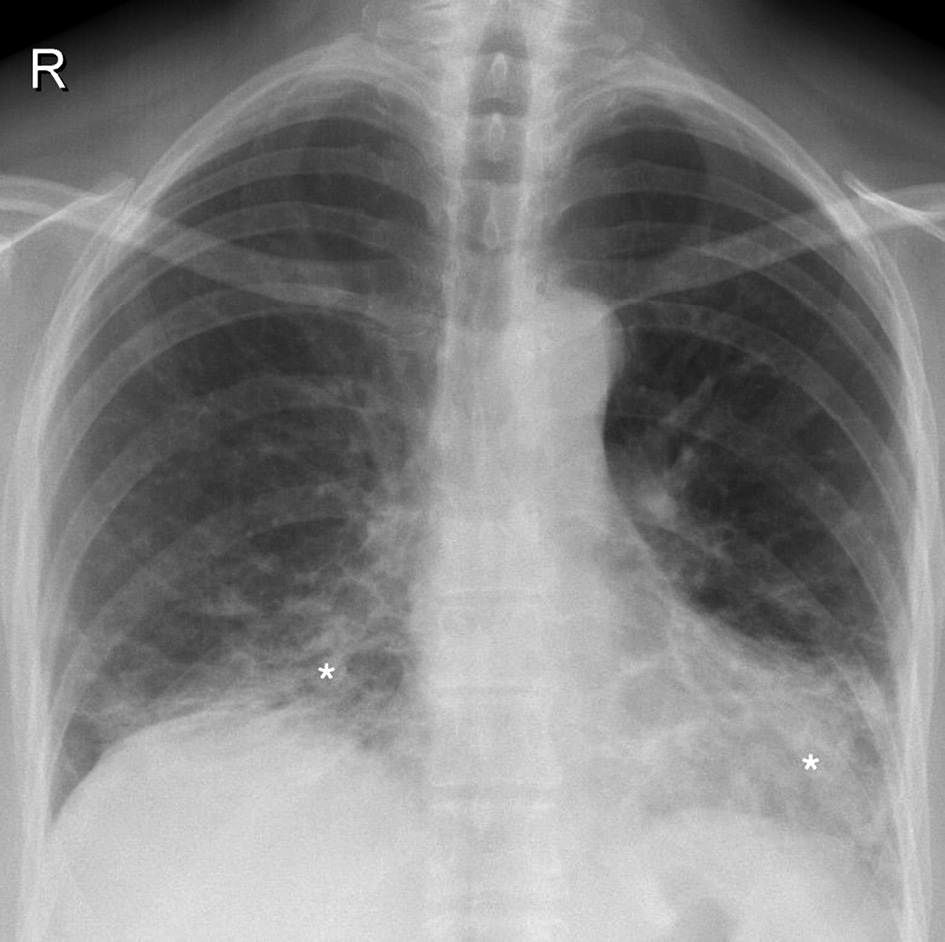

Due to progressive dyspnea, further management of the patient was continued in our department. Physical examination revealed a respiratory rate of 19 times per minute in rest and tachypnea during light physical activity (respiratory rate greatly elevated and was immeasurable). In auscultation, no audible rales and normal vesicular breathing were inspected. Peripheral blood oxygen saturation (SpO2) on room air was 95% in rest and 82–85% during light physical activity. With oxygen supply, SpO2 increased to 90–92%. Arterial blood gas examination showed partial oxygen pressure of 70.7 mmHg. Pulmonary function assessment demonstrated restriction and minor gas diffusion impairment (FVC 3.00 (72%), FEV1 2.55 (69%), FEV1/FVC 79%, TLC 5.03 (70%), VC 2.98 (72%), RV 1.82 (76%), RV/TLC 79%, DLCO 8.1 (62%)). Control chest roentgenography showed remaining signs of interstitial disease, mostly in the lower lobes (Figure 2).

Figure 2. Control chest roentgenogram (2020.02.12) showing bilateral interstitium infiltration (white asterisks) predominantly in the lower segments and focal infiltrative opacities.